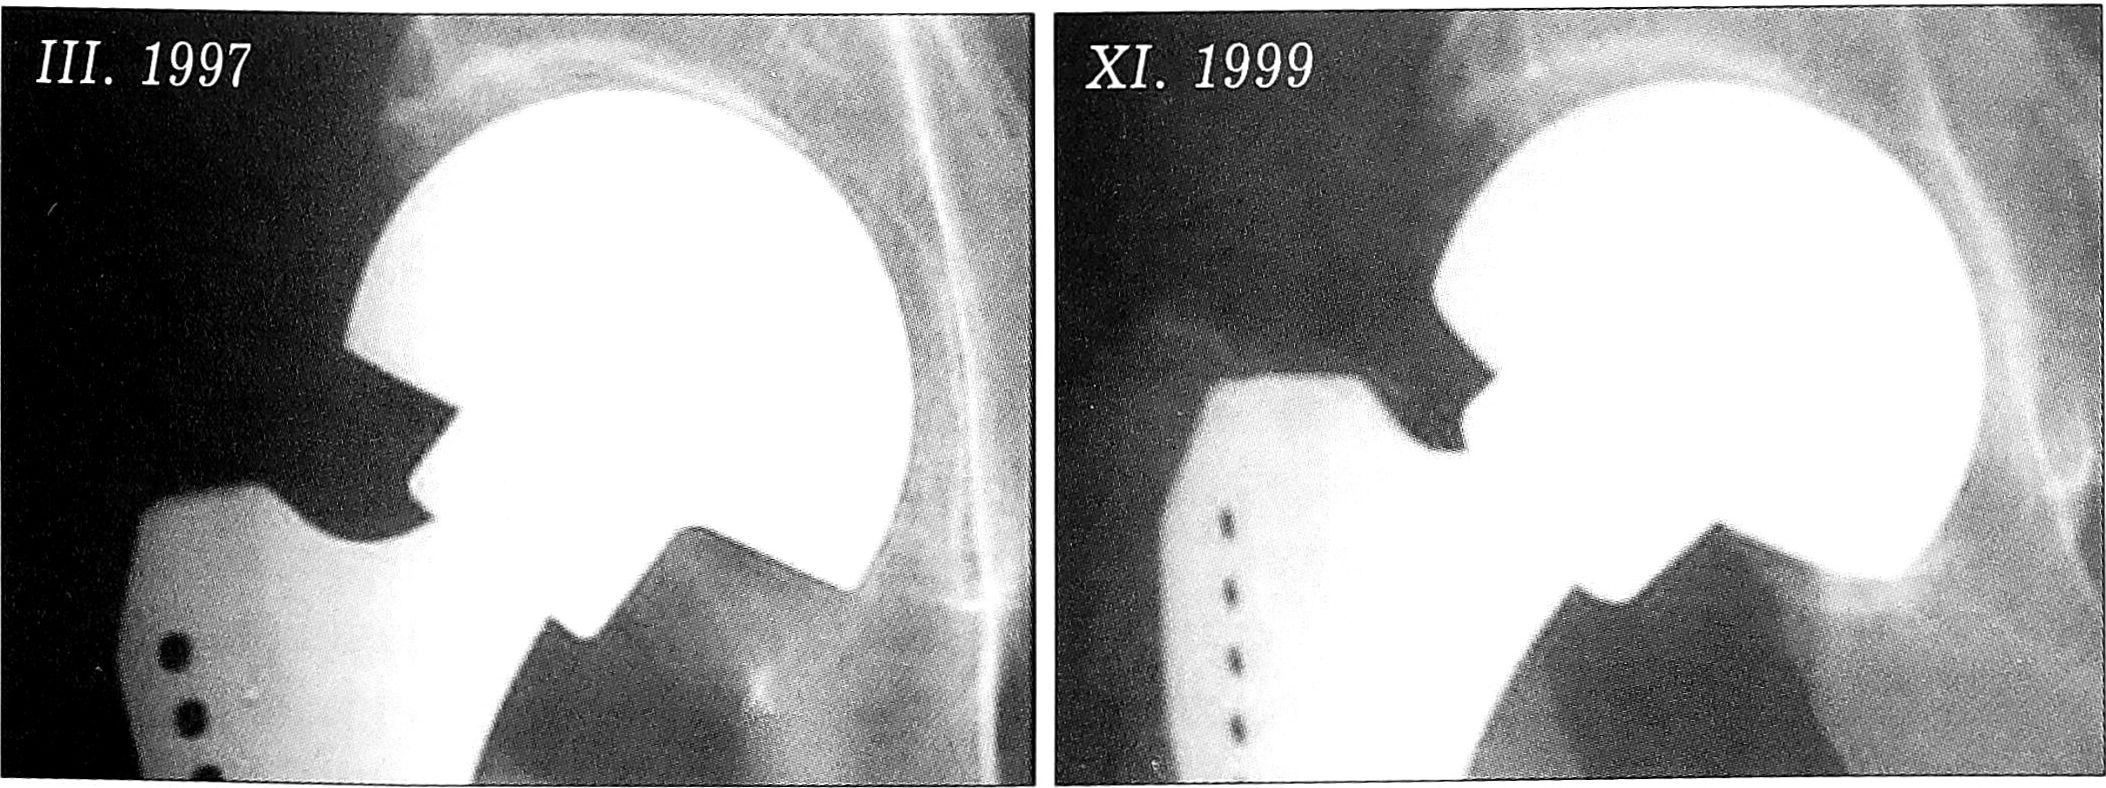

Использование монополярных эндопротезов имеет свои положительные стороны — низкая стоимость конструкции, простота, меньшая травматичность и продолжительность операции, однако при этом чаще отмечается расшатывание ножки протеза (при применении устаревших моделей) или протрузия его головки в вертлужную впадину (рис. 1).

Рис. 1. Развитие протрузии головки эндопротеза Мура—ЦИТО в вертлужную впадину в течение 5 лет.

Использование биополярных эндопротезов современных конструкций также далеко не всегда предотвращает развитие протрузии головки в вертлужную впадину, наиболее часто это связывают с остеопорозом (рис. 2). Вместе с тем в ряде случаев монополярные эндопротезы служат в течение длительного времени без признаков развития нестабильности или протрузии и переживают современные тотальные эндопротезы цементной фиксации, установленные с помощью техники цементирования II генерации, наиболее распространенной в нашей стране (рис. 3).

Рис. 2. Протрузия биполярной головки в вертлужную впадину в течение 2 лет.